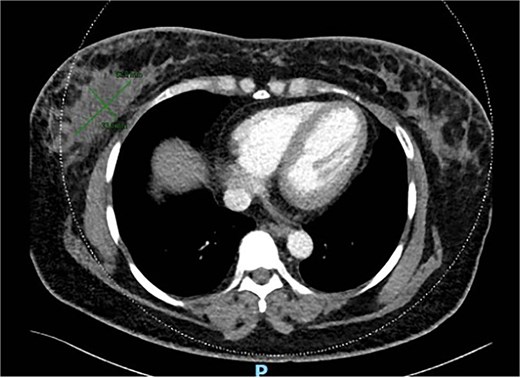

She underwent excision biopsy of the 80 mm right breast siliconoma in Aug 2021. Histology showed 80 mm invasive mammary carcinoma with apocrine component. GATA 3 positive, CK7 positive. Estrogen receptor (ER) and progesterone receptor (PR) negative and cerB2 positive. Margins were involved anteriorly, superiorly and posteriorly. Staging computed tomography (CT) scan showed multiple nodules scattered in both breasts and post-surgical seroma including a lobulated and enhancing soft tissue in retro-areolar region (Fig. 7). No metastasis noted.